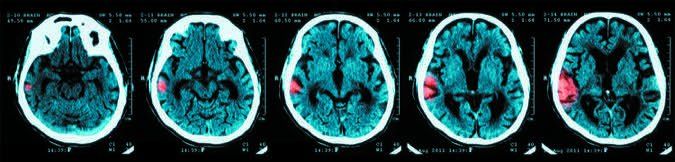

Stroke is among the leading causes of death in the U.S., but it is still a misunderstood health condition. Plenty of myths and misguided ideas surround stroke, from its causes and symptoms to its potential severity and the particulars of recovery. To help clear up some misunderstandings, Efrain Salgado, MD, director of the Cleveland Clinic Florida Stroke Center and Neurosonology Laboratory, explains the truth about 10 common stroke myths